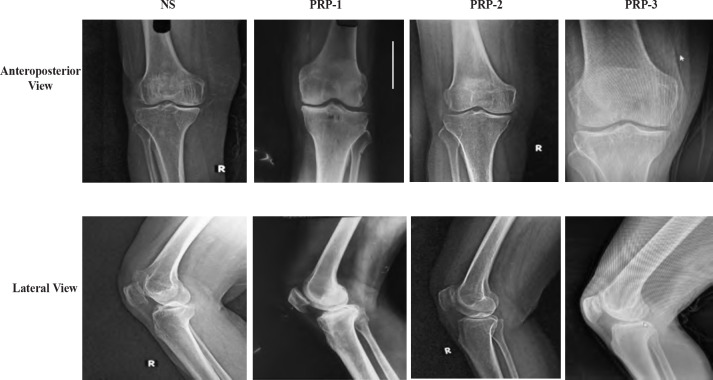

Material and methods: A total of 130 patients were randomised into 4 groups; PRP-1 (n=36), PRP-2 (n=34), PRP-3 (n=32) and saline (NS) (n=28), after approval from institute ethics committee (reference number: TMU/IEC/20-21/091) and was conducted in accordance with Helsinki declaration. Groups PRP-1, PRP-2, PRP-3 received single, double and triple injections of PRP whereas NS group received single saline (0.9%) injection. Assessment of outcome scores (visual analogue scale [VAS] and Western Ontario and McMaster Universities Arthritis Index [WOMAC]) was done at baseline and three, six, nine months post intervention. Serum collagen 2-1 (Coll2-1) estimation at baseline and nine months post-therapy was used for biochemical assessment.